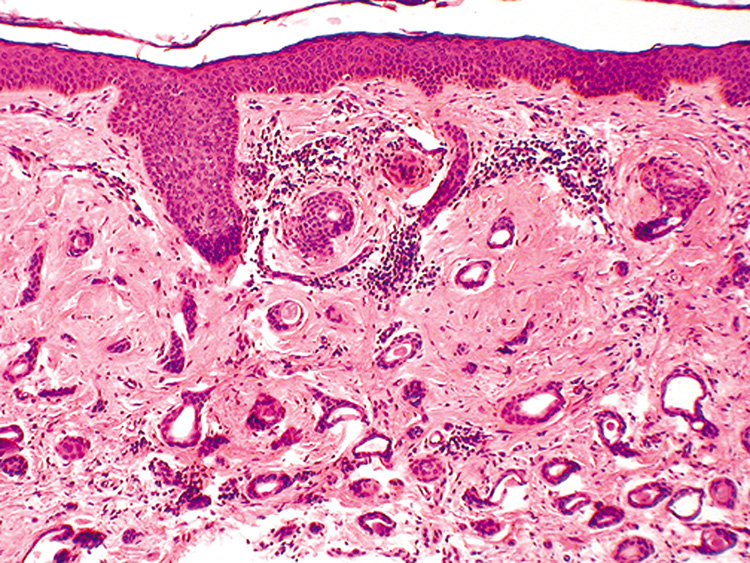

Verruca vulgaris (warts) are caused by a variety of papilloma viruses and may present as small papules with a digitated surface or elongated filiform warts around the eyes. Histologically, they demonstrate varying degrees of massive papillomatosis, hyperkeratosis, and acanthosis with parakeratosis and collections of serum in the stratum corneum at the tips of the digitations (Fig. 8). In early warts, the keratinocytes in the granular layer and just beneath the granular layer are vacuolated with condensation and clumping of dark-staining keratohyaline granules and occasional eosinophilic inclusion bodies in the nuclei.

Fig. 8. Verruca Vulgaris—A. Low-power photomicrograph illustrating papillomatous growth with a fibrovascular core, hyperkeratosis, and acanthosis (hematoxylin and eosin stain). B. High-power photomicrograph demonstrating intranuclear viral inclusion (black arrow) (hematoxylin and eosin stain). (Photos courtesy of William Morris, M.D.)